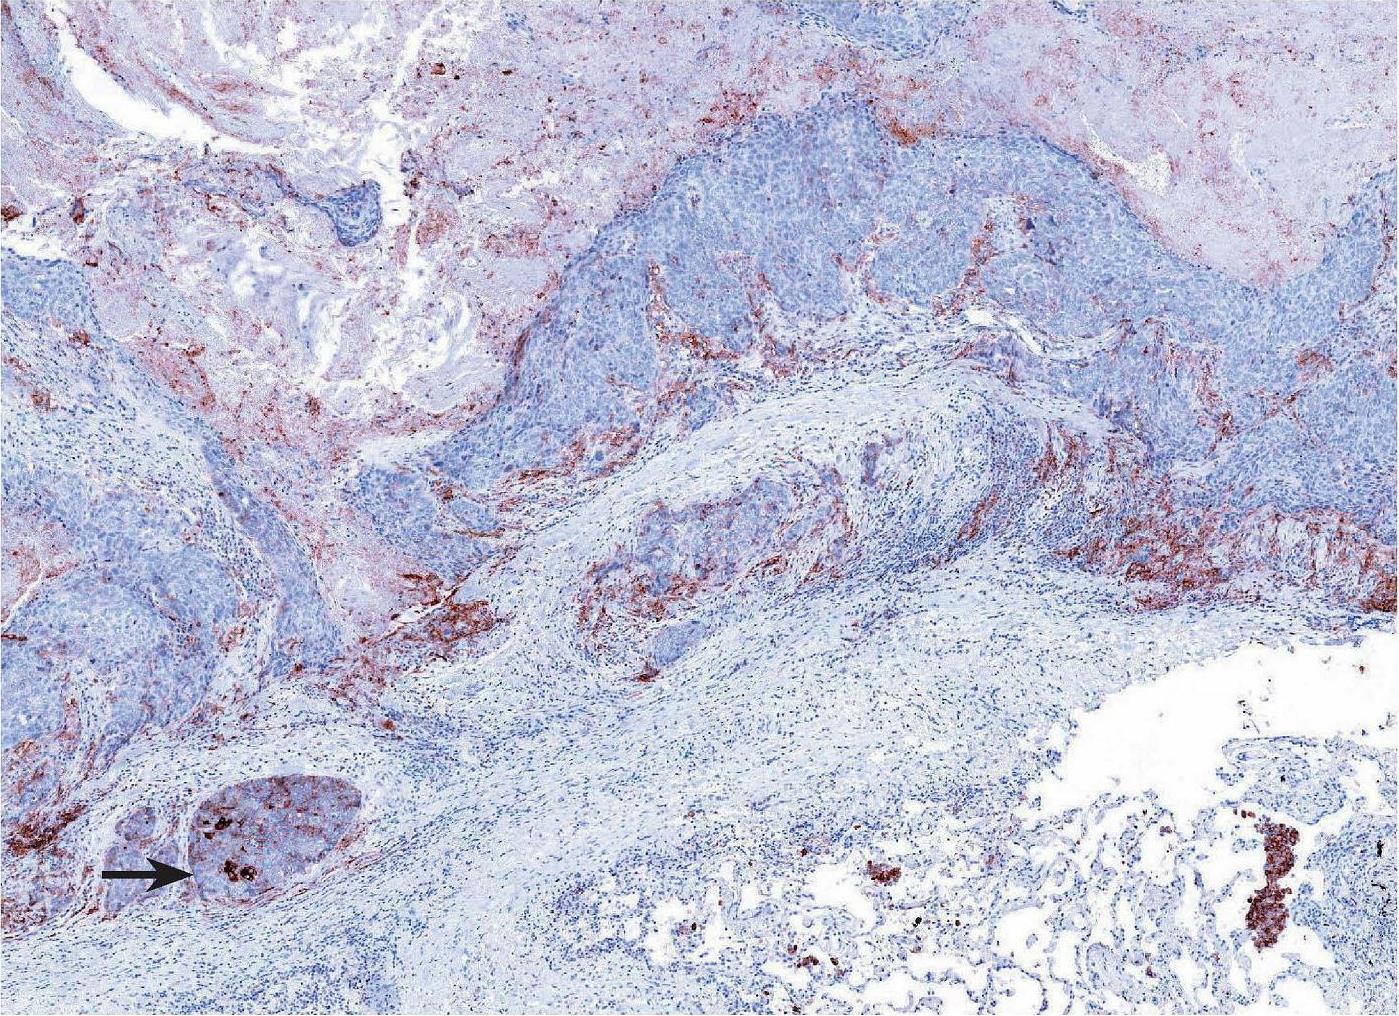

图2-2 PD-L1在肿瘤区域内呈异质性表达 [5]

注:在低倍镜下,按照肿瘤细胞数量相对均等的原则将肿瘤大致分为4个区域,分别计算4个区域PD-L1的TPS值后取平均值即为PD-L1最终结果。4个区域的TPS评分分别为80%、50%、25%和100%,整个肿瘤PD-L1 TPS评分最终为(80%+25%+50%+100%)/4=63.75%。因此,该病例TPS>50%